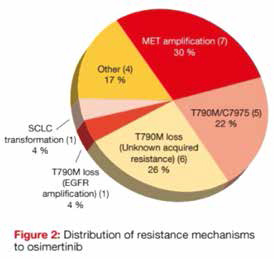

奥希替尼耐药机制研究

奥希替尼耐药机制研究

2019-10-15 08:43:16

法国研究者Mehlman等报告,在携带EGFR突变的晚期非小细胞肺癌(NSCLC)患者中,奥希替尼是有效的;在疾病进展时,最常见的分子改变为MET扩增和C797S突变。(Lung Cancer. 2019…